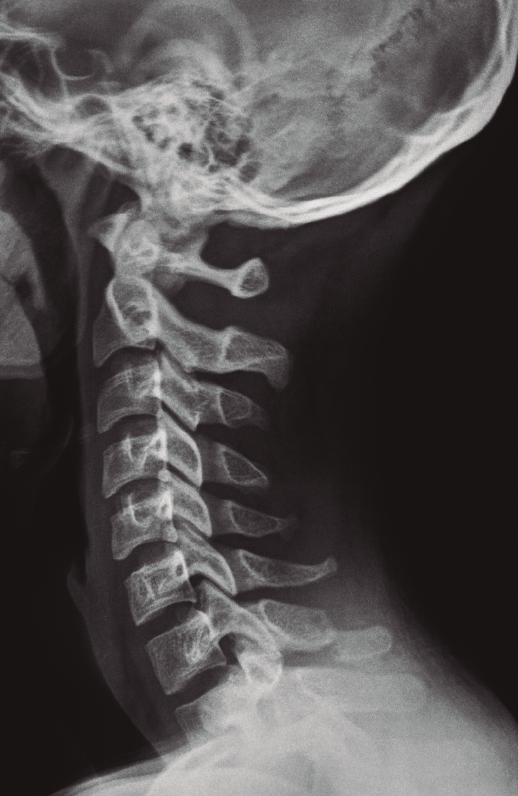

Figura 1. Fractura de la apófisis espinosa de C7.

Se solicitó estudio radiográfico(3) y tomografía computarizada (TC)(4) de la columna cervical donde se apreció una fractura con ligera desviación de fragmentos de la apófisis espinosa de C7 (Figuras 1 y 2).

Figura 2. Fractura con ligera desviación de fragmentos de la apófisis espinosa de C7.